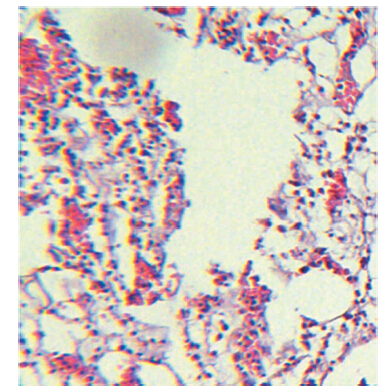

高倍显微镜下,A组可见骨组织无明显水肿,大片死骨形成,呈片状或条带状,伴或不伴有少量成骨母细胞,呈零星点状分布,未见明显分布规律,其中1例稀疏凌乱排列着少量嗜酸性粒细胞,见图 4。B组均可见骨组织轻度水肿,无死骨形成,其中4例可见大块区域的嗜酸性粒细胞浸润,面积较大伴组织水肿,符合慢性骨髓炎改变,且成骨细胞更稀疏,见图 5。C组可见组织肿胀,成骨细胞散在分布,其中8例可见大块区域的嗜酸性粒细胞浸润性生长,面积较大,组织明显水肿,细胞成分较为混乱,见图 6。病理学检测结果与细菌学结果相符。

图 4 经蒸馏水煮沸杀菌的兔慢性骨髓炎胫骨组织病理学检查结果(苏木素-伊红染色,A×100、B×50)片状或条带状明显死骨形成(箭头所指),但未见嗜酸性粒细胞等炎症细胞存在 |